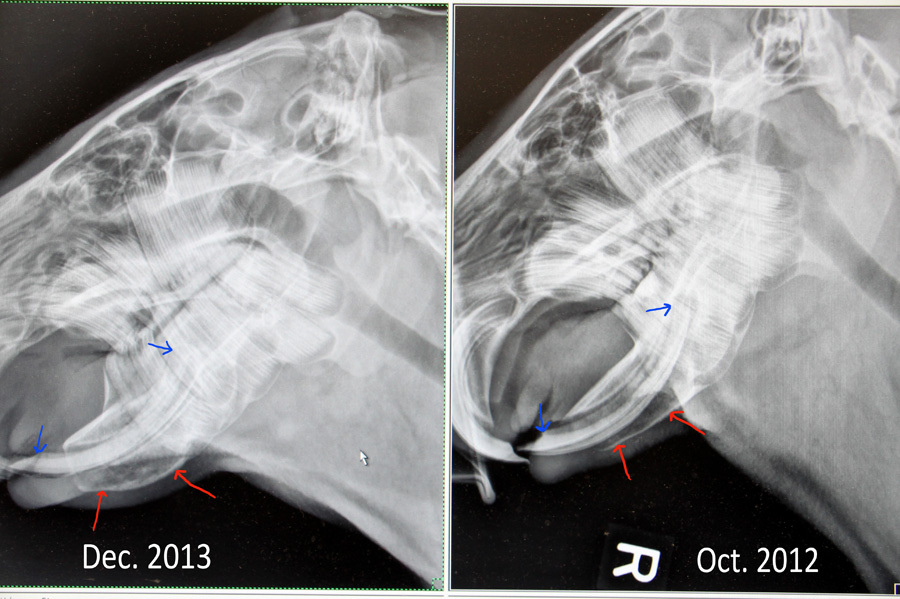

When Melanie adopted Gari, he was malnourished and very underweight: at 10 months he weighed only 45 pounds. By the time he was 1-1/2 years old, his weight had increased to 84 pounds, nearly that of a wild capybara his age. However, possibly due to the lack of sunlight those first 10 months, his bone density is not good enough to securely hold his teeth and a tooth had rotated in his jaw. It became infected and the infection has now entered his jaw.

Left- Current condition, with distended, infected jaw. Right- One year ago, the jaw looks nice and clean.